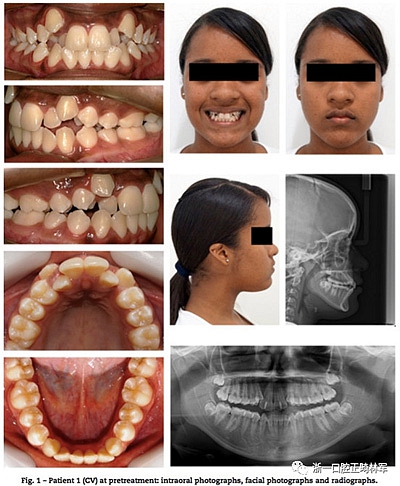

13歲雙胞胎女性患者,安氏II類(lèi)錯(cuò)合畸形伴嚴(yán)重上頜牙列擁擠,異位尖牙。臨床檢查提示雙胞胎患者情況類(lèi)似,如:側(cè)貌、長(zhǎng)面型、中等頰廊及唇肌松弛。不同點(diǎn)有:一名表現(xiàn)為露齦笑,右上頜側(cè)切牙空間不同(圖1,2),頭影測(cè)量指標(biāo)見(jiàn)表1。